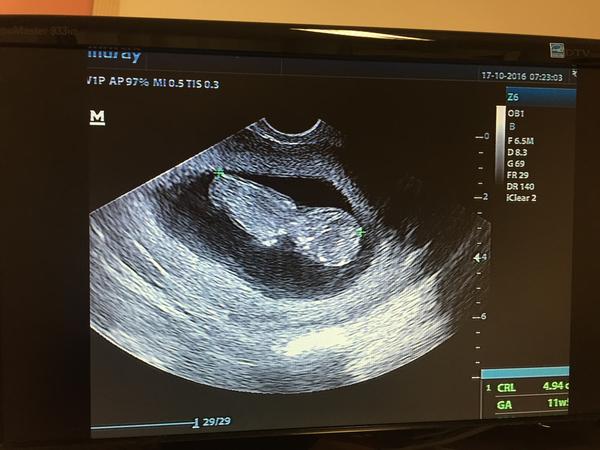

Ahojteeeee tak dnes sme ráno boli po 3 týždňoch u Dr. Priniesla som 2x sterilný moč, zobrali mi 5 ampuliek krvi a dostala som tehotenskú knižku 🙂 Podľa posledného sona sme dnes mali byť v 10+6 tt a podľa dnešného sona sme 11+5 tt a máme 4,9 cm. Drobčátko si spokojne spinkalo 🙂 Merala ho najprv z predu ( škoda že tú foto nemám, tá bola lepšia) a potom ho chcela zmerať aj z profilu ale krpec nie a nie sa pohnúť tak sme ho museli trošku prebudiť :D Bolo to strašne miléééé 🙂 31.10. idem na ultrazvuk a 14.11. na ďalšiu poradňu.